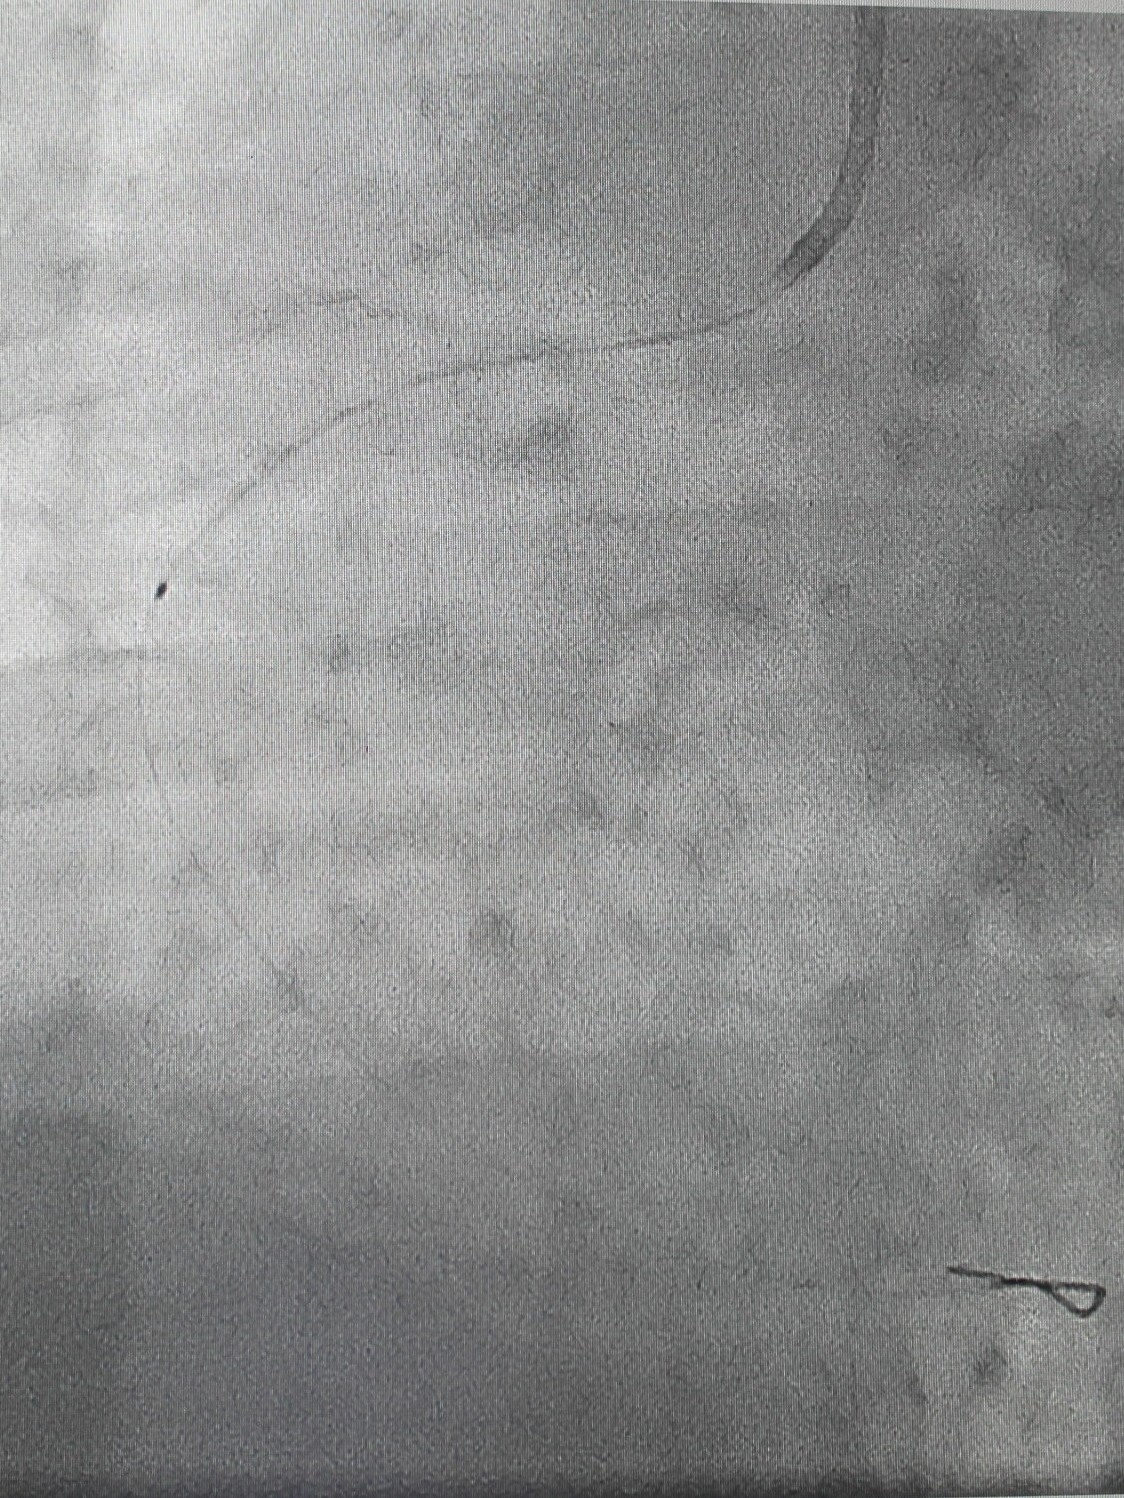

По экстренным показаниям проведена коронароангиография, выявлено стенозирующее многососудистое поражение: стеноз (сужение) передней межжелудочковой ветви левой коронарной артерии 80% в проксимальной трети, стеноз огибающей ветви 75% в дистальной трети (при том, что существенным рассматривают сужение артерии > 50%), тромботическая окклюзия правой коронарной артерии (в проксимальной трети). Рентгенхирурги выполнили тромбэкстракцию из правой коронарной артерии, баллонную ангиопластику со стентированием правой коронарной артерии (2 стента с лекарственным покрытием). Операция продолжалась около часа, после чего пациент продолжил лечение под наблюдением врачей отделения кардиореанимации; через двое суток был переведен в отделение кардиологии для дальнейшего лечения.

| Обнаружены участки стенозирования артерии | Установлены 2 стента, стенты раскрыты | На контрольной ангиограмме: коронарный кровоток восстановлен, раскрытие стентов полное, позиционирование адекватное |